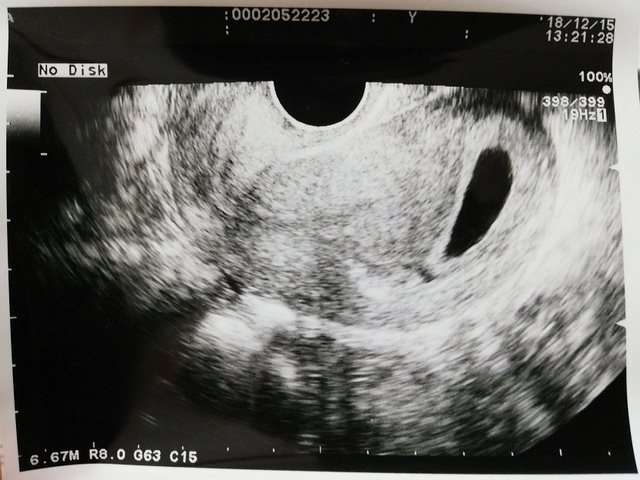

6週3日(6w3d・性別不明)|nori1515 さん(31歳)

エコー写真撮影時のエピソード:

前の週から急に吐き気とムカムカするつわりのような症状が続き、検査薬で陽性も出ていたので妊娠かなと思ってはいましたが、実際産婦人科受診するまではうれしさと同時に無事妊娠してるのかな、子宮内妊娠だろうかと不安な感情が大きかったように思います。産婦人科でエコー写真を見たとき、7mmという小ささの赤ちゃんが見えてやっと私たちのもとに来てくれたんだととてもうれしかったのを覚えています。主人もとても喜んでくれて、喜ぶ顔を見たらつらいつわりも頑張って乗り越えようと強く思いました。まだ安心は出来ないけど、このまますくすく大きくなるのを祈りつつ、安静に過ごしていきたいと思います☺️